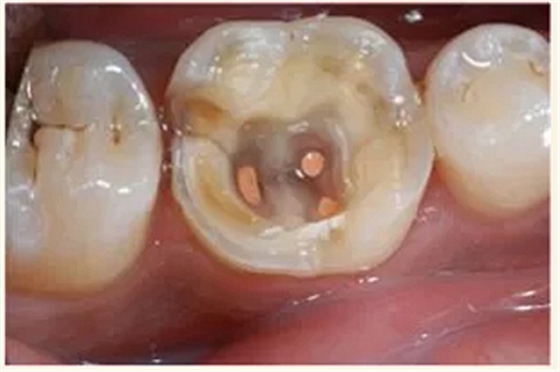

根管治療術(shù)又稱牙髓治療,是牙醫(yī)學(xué)中治療牙髓壞死和牙根感染的一種手術(shù)。該手術(shù)保留了牙齒,先是揭開髓室,頂敞開通路,用拔髓針拔除感染的牙髓。在用擴(kuò)挫針擴(kuò)凈根管壁,之后在根管內(nèi)封消炎藥,最后再用牙膠尖充填,手術(shù)繁瑣,一般要2-4次就診才能完成。隨著技術(shù)和材料的進(jìn)步,活髓牙一次性根管治療術(shù),也在臨床應(yīng)用。